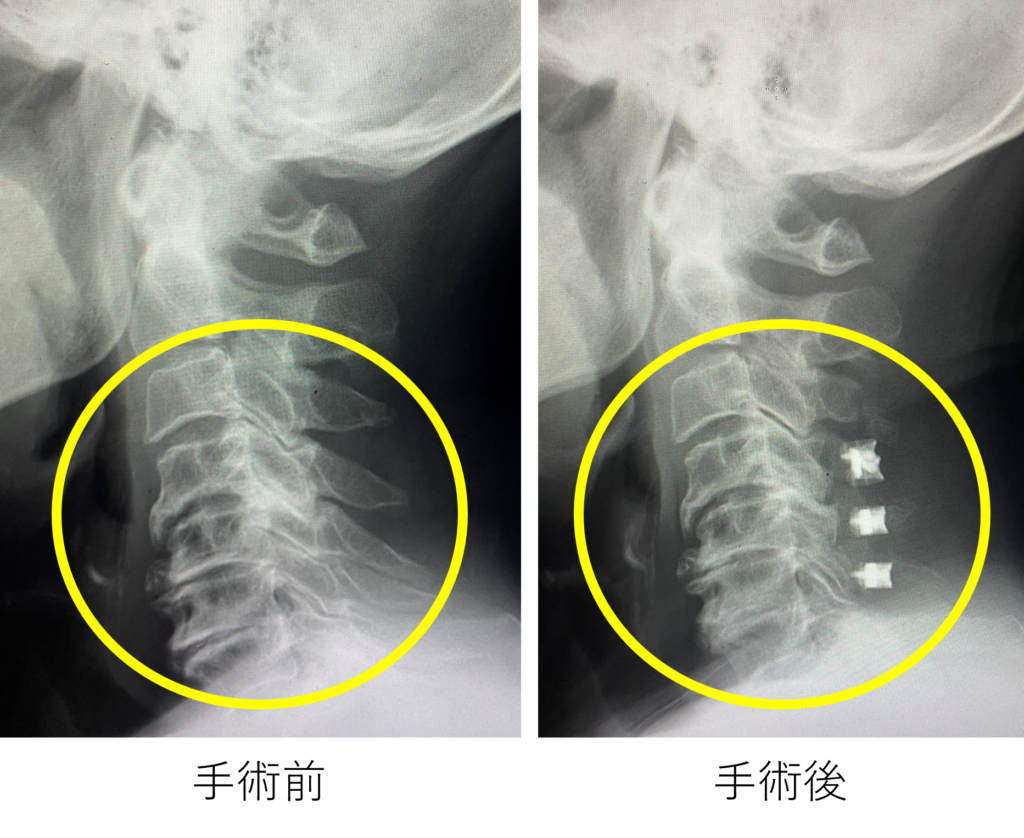

前方到達法 【頚椎前方除圧固定術】

神経を圧迫する変形した椎間板や骨の変性部分を摘出し、神経の除圧を充分に行い、代わりに骨の支えとなる金属(ケージと呼ばれます)を置きます。椎間板ヘルニアの摘出や、変形した頚椎の矯正、また神経の圧迫の解除にも有効な手術です。 前頚部に4cm程度の皮膚切開を必要とします。入院期間は1週間前後です。